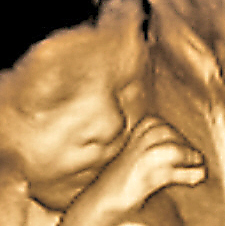

香港结构超声波照片

结构性超声波, 四维 香港, 四维结构性超声波 结构性超声波, 四维 结构性超声波, 四维 香港, 四维结构性超声波 结构性超声波, 四维 香港, 四维结构性超声波 结构性超声波, 四维 结构性超声波, 四维 结构性超声波, 四维 香港, 四维结构性超声波 结构性超声波, 四维 香港, 四维结构性超声波 结构性超声波, 四维 结构性超声波, 四维